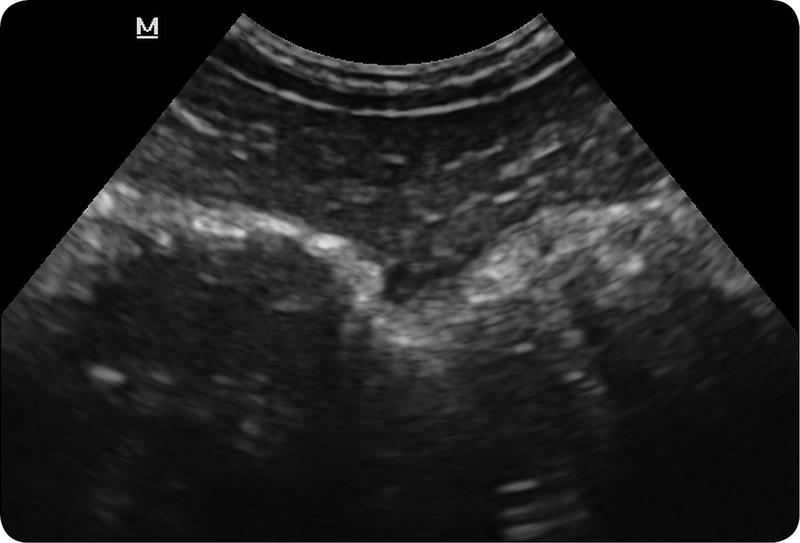

Kiedy omawiamy diagnostykę raka jelita grubego, warto zwrócić uwagę na dostępne opcje – począwszy od badań obrazowych, a kończąc na endoskopii. Na początek przyjrzyjmy się ultrasonografii (USG). Choć na pierwszy rzut oka wydaje się to znakomitym rozwiązaniem, to w rzeczywistości niespecjalnie sprawdza się jako pierwszy wybór, ponieważ ma swoje ograniczenia. USG dobrze zadziała w przypadku dużych guzów, ale jeżeli chodzi o wczesne etapy nowotworu, niestety, nie jest wystarczająco efektywne! Dlatego, jeśli chcesz naprawdę zdziałać cuda w diagnostyce, umów się na wizytę do swojej gastroenterolog i dopytaj o kolonoskopię. Ta metoda polega na bezpośrednim spojrzeniu na wnętrze jelita, a co najlepsze – jeśli lekarz natrafi na polipy, ma możliwość ich natychmiastowego usunięcia. Prosto, wygodnie, a na dodatek można potem zrobić świetne selfie z ekranu!

Ultrasonografia, znana w skrócie jako USG, stanowi jedno z badań, które od razu przychodzi na myśl, gdy rozważamy diagnostykę medyczną. Warto jednak zauważyć, że kiedy mówimy o wykrywaniu nowotworów, szczególnie raka jelita grubego, USG nie pokazuje pełni swoich możliwości. Ma swoje ograniczenia, zwłaszcza w przypadku małych zmian, a diagnostyka wczesnych stadiów nowotworów nie zagwarantuje najlepszych wyników. Możemy porównać USG do dobrego kucharza, który przyrządza znakomity obiad, ale zapomniał o soli – wszyscy odczuwają, że czegoś brakuje, ale nikt nie potrafi dokładnie zidentyfikować problemu.

W dodatku obrazowanie ultrasonograficzne charakteryzuje się szczególnymi cechami. Z łatwością wykrywa duże guzy, które mogłyby nawet zabierać głos w karaoke, natomiast rozpoznawanie subtelnych, małych zmian, które mogą w przyszłości przekształcić się w nowotwory, sprawia jej trudności. Dlatego poleganie wyłącznie na USG w kontekście wykrywania raka jelita grubego przypomina kupowanie losu na loterii – lepiej mieć różne metody w zasięgu ręki, aby zwiększyć swoje szanse na sukces. Warto więc rozważyć takie alternatywy, jak kolonoskopy, tomografy komputerowe czy rezonanse magnetyczne, które dostarczają znacznie więcej informacji niż wywiad w programie plotkarskim.